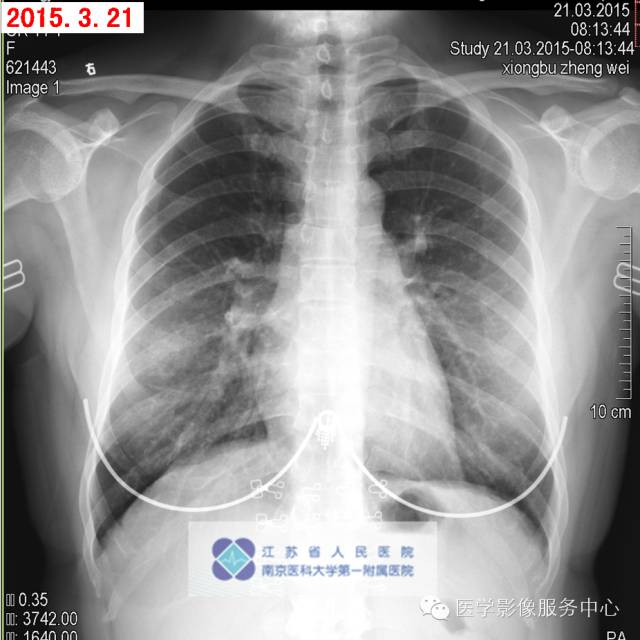

女性,31岁,患者受凉后出现咳嗽,少量黄痰,伴咽喉痛,早晨起床症状明显,咳嗽时伴后背不适,自服头孢类抗生素,症状有所缓解,渐出现胸闷,无体力活动受限,至我院急诊就诊。

影像分析:右中肺团片状磨玻璃影,境界清晰:纤维组织增生?原位肿瘤?其他?